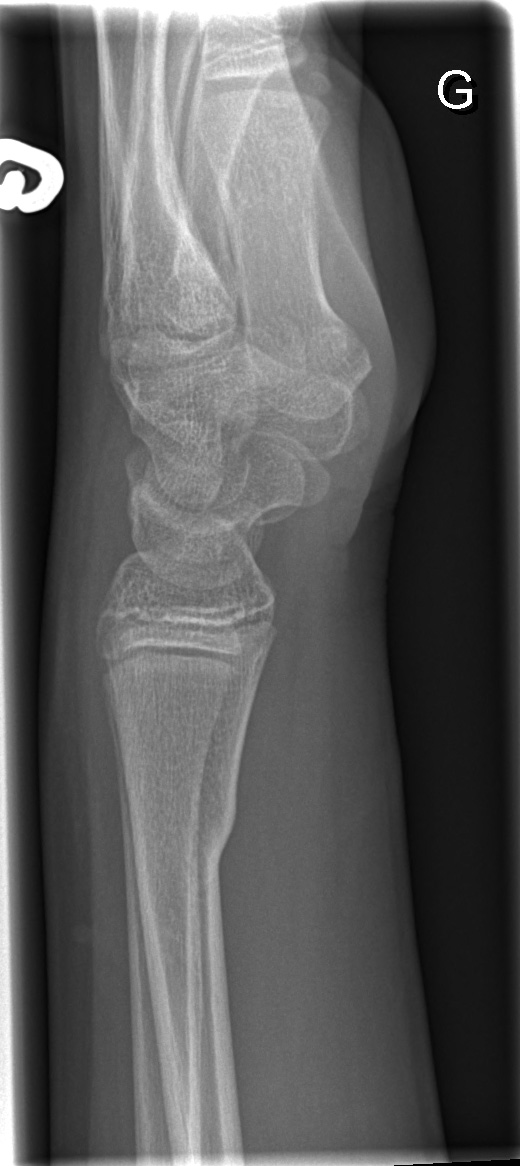

12-year-old male:

Left wrist pain after falling on a hyperextended arm and a flexed wrist.

Metaphyso-diaphyseal transverse fracture of the distal radius involving mostly the volar cortex.

Broken dorsal cortex

This is not a torus fracture since the dorsal cortex is also broken. This is not a greenstick fracture either (a bending plastic deformity of one cortex and a tension fracture of the opposite one).

Lateral